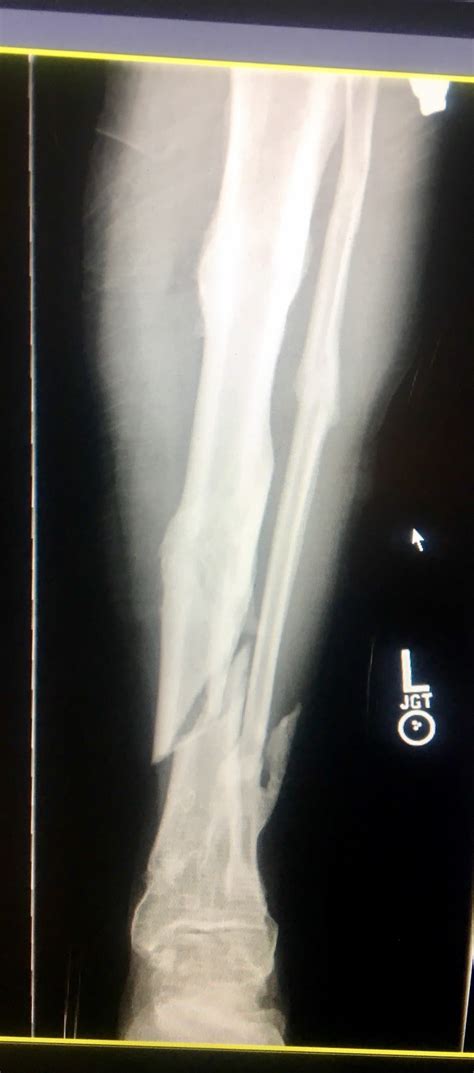

When will i be able to walk without crutches and when will i be able to walk without a limp. After tibial plateau fracture surgery you will experience pain, swelling, stiffness and decreased range of movement in your knee. A fracture is another word for a break. There is normally a recent history of trauma to the knee. People should always follow their doctor's recommendations about returning to walking, exercising, and other physical activity after a leg fracture. Most importantly, by this stage you should not have any residual pain other than an ache and some stiffness when you wake. People are generally unable to walk. (obq09.166) a large posteromedial tibial plateau fracture pattern, as seen with the bicondylar tibial plateau fracture shown in figures a and b, is important to recognize because of which of the following factors? He didn't give me any other instructions other than i worked the next several weeks on my limp and stamina. Tibial plateau fracture with metal plate fixation. Tibial fractures are common and usually caused by an injury or repetitive strain on the bone. Tibial plateau fractures occur just below the knee joint and can involve the cartilage surface of the knee. At this stage, after eight weeks of rehab exercise, it's worth trying to determine what someone with a tibial plateau fracture should be able to do and should not attempt to do. Avulsion fracture of margin of lateral tibial plateau just below joint line. Proper identification and management of these injuries will help to restore limb function. Active flexion and passive extension are encouraged for 6 weeks, after which period active. Pcl and lcl associated with medial plateau fracture.